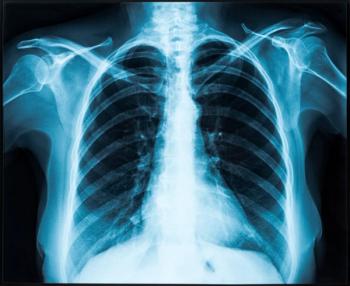

Patients should describe their symptoms in detail and seek early care for suspected lung cancer, especially since the disease may resemble pneumonia and bronchitis on imaging tests.